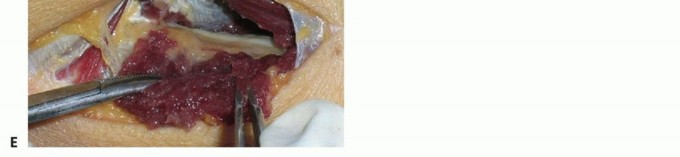

The crux of the procedure is the release of the Arcade of Frohse and the superficial head of the supinator. Using a right-angle clamp, a protective pathway is created deep to the Arcade, superficial to the PIN. The aponeurotic edge and the entire length of the superficial supinator muscle belly are then sharply divided using a scalpel or scissors. This release must extend completely to the distal margin of the supinator to ensure no hourglass constriction remains. As the muscle is divided, the surgeon will observe the PIN lying on the pristine deep head of the supinator.

Image